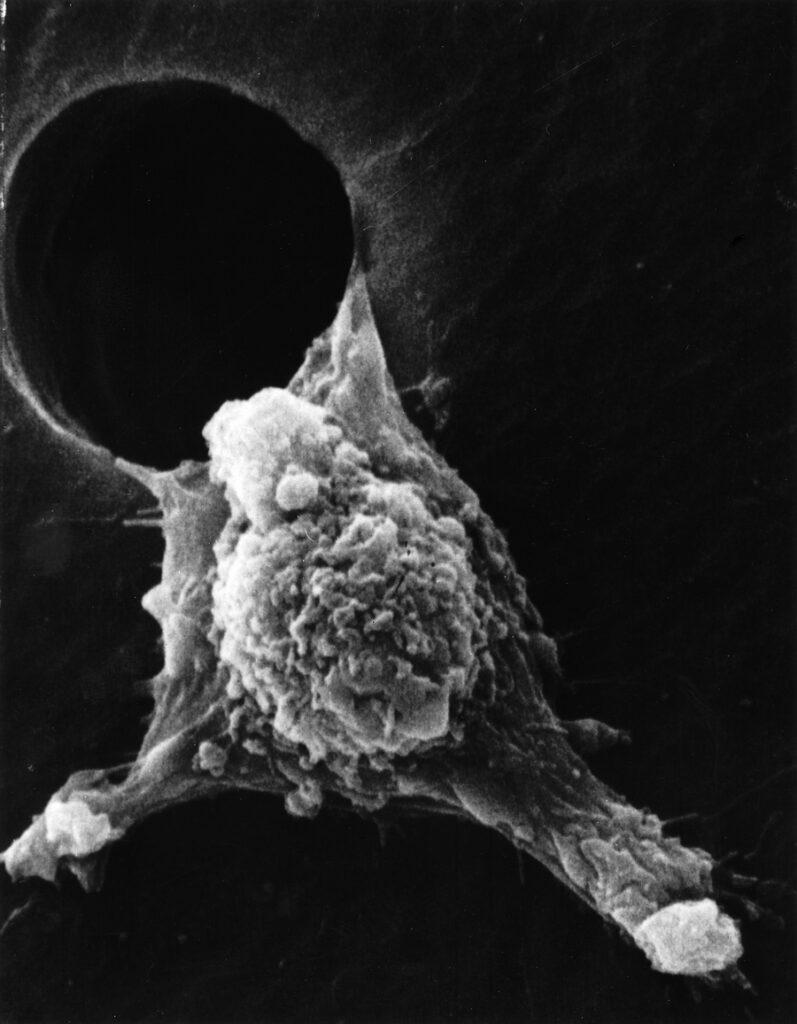

Раковая шишка – это заболевание, которое поражает кожу и слизистые оболочки. Она может возникнуть в различных частях тела и иметь различные внешние проявления. В данной статье мы представляем вам многочисленные фотографии раковых шишек, чтобы вы могли узнать, как они выглядят.

Одной из наиболее распространенных локализаций раковых шишек является лицо. На фото вы можете увидеть различные типы раковых шишек, такие как базалиома, плоскоклеточный рак и меланома. Обратите внимание на характерные признаки каждого типа раковой шишки, такие как изменение цвета, формы и размера.

Раковые шишки могут возникать не только на лице, но и на других частях тела. На фотографиях вы можете увидеть примеры раковых шишек на шее, руках, ногах и туловище. Обратите внимание на различные формы и размеры раковых шишек, а также на их внешний вид.